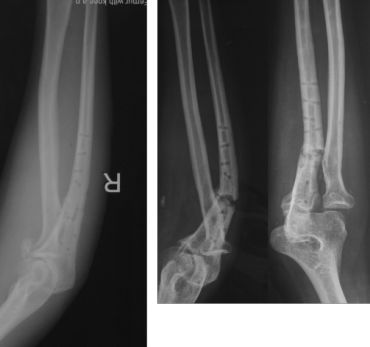

点评:可能的原因手术不当,剥离过多而没有植骨;钢丝多此一举;康复不利关节僵硬。骨质疏松提示功能不好。取出钢板骨断裂,取出后片子显示骨折愈合不良;因为功能差桡骨头切除

教训:新鲜孟氏骨折尺骨复位桡骨头即可复位,必要时修复外侧韧带。早期功能锻炼很重要。近关节的骨折愈合不好关节僵硬取出内固定后更容易断裂;不熟悉的方法要有人指导或不用。钢丝代替环韧带有适应症,不适合新鲜骨折。